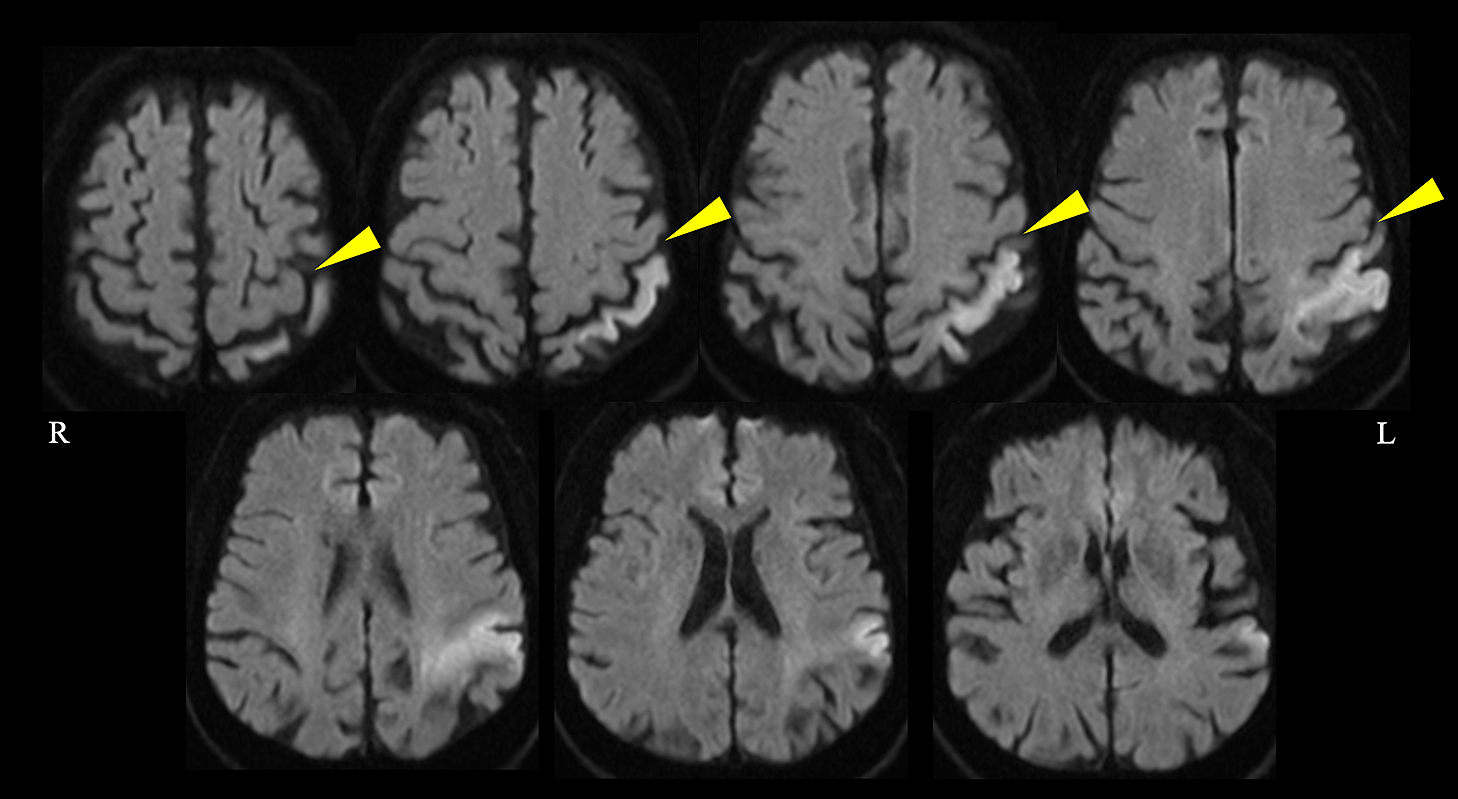

直接経口抗凝固薬内服にもかかわらず脳梗塞を発症した心房細動患者に対する経皮的左心耳閉鎖術:症例報告

Percutaneous left atrial appendage closure for atrial fibrillation-related ischemic stroke despite direct oral anticoagulation: a case report

川端 健新, 江頭 柊平, 村松 恭祐, 逸見 文昭, 宇羽野 恵, 小西 明範, 大森 奈美, 山口 徹雄, 児玉 隆秀, 上坂 義和

Kenshin Kawabata, Shuhei Egashira, Kyosuke Muramatsu, Fumiaki Henmi, Megumi Ubano, Akinori Konishi, Nami Omori, Tetsuo Yamaguchi, Takahide Kodama, Yoshikazu Uesaka

2026/02/13